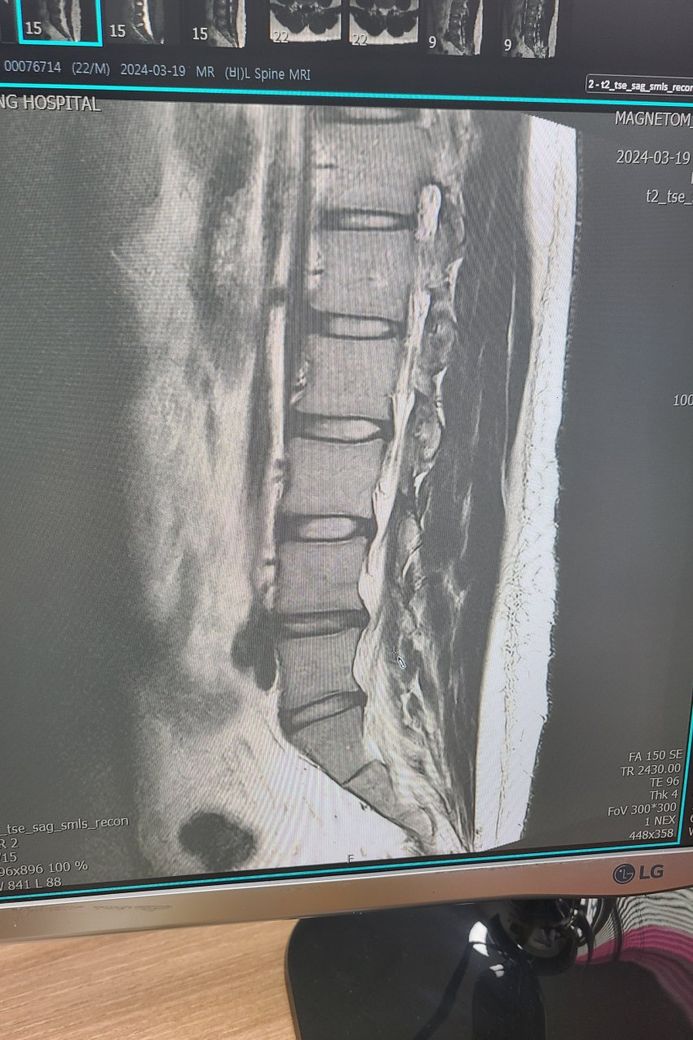

1. 사진상에서 4번 5번 뼈쪽 사이에 디스크가 있는데 키가 줄었을까요????

Mri 이미지를 보면 L4-L5 사이 디스크가 돌추로디어 있어 허리디스크 소견이 보입니다 이 부위 디스크가 눌리면 허리 통증, 엉치/다리 저림 증상이 나타날 수 있습니다 키가 줄었을 가능성이 있어요 디스크가 눌리면서 추간 공 높이가 줄어들면 척추 길이도 감소할 수 있기때문입니다.

해당 사진만으로 척추 측만증 여부를 판단하기 어렵습니다!